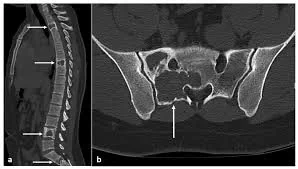

A tomografia computadorizada também é eficaz, porém apresenta menor qualidade de imagem e emite radiação. Deve ser utilizada quando a ressonância não é possível, na suspeita de lesões ósseas associadas, calcificadas ou processos expansivos.

Tomografia de coluna lombar demonstrando áreas de degeneração discal e hérnias extrusas

Tomografia demonstrando áreas de degeneração discal e hérnias discais extrusas — setas vermelha e azul.

Tomografia de coluna lombar demonstrando lesão óssea associada

Tomografia de coluna lombar demonstrando lesão óssea (seta branca).